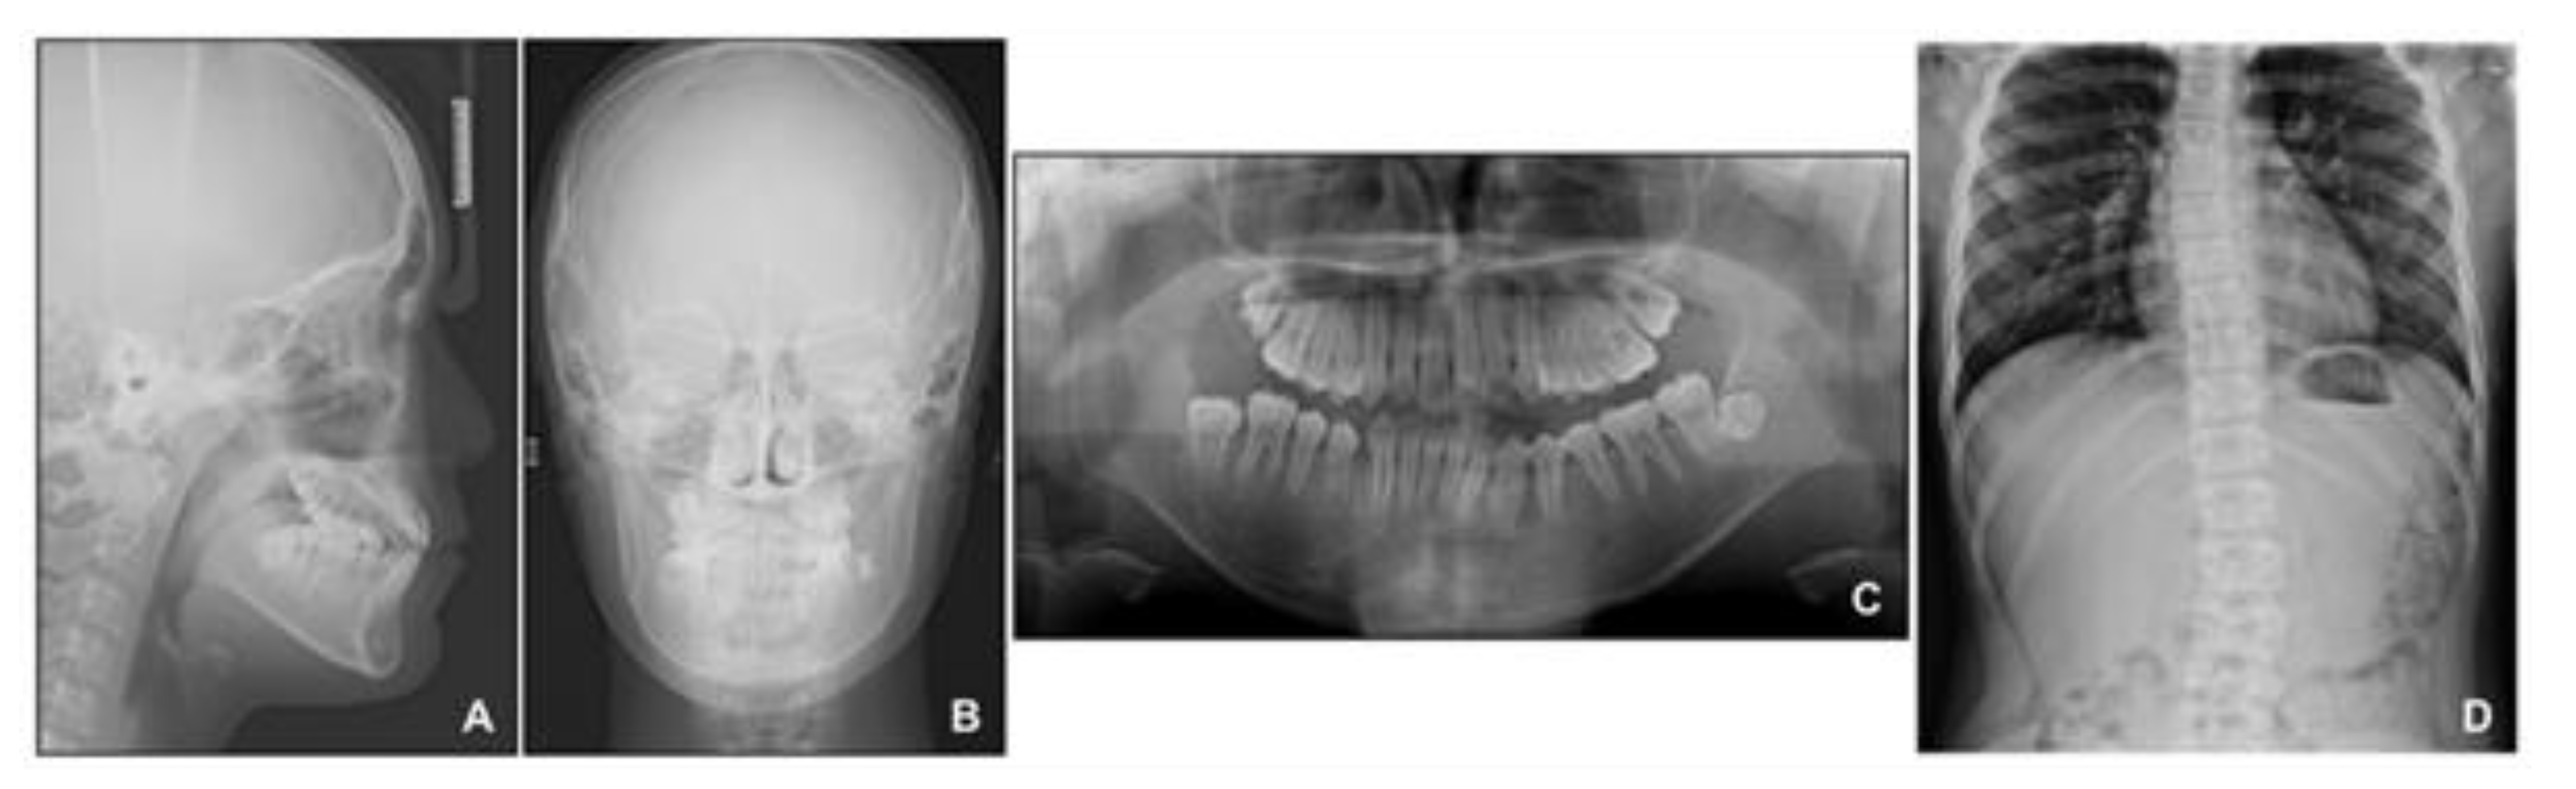

Figure 8. Radiographs before phase 2 treatment: (A) Lateral cephalogram; (B) Posteroanterior cephalogram; (C) Panoramic radiograph; (D) Standing anteroposterior radiograph of spine showing scoliosis.

When the patient reached 13 years of age, he claimed that his teeth were still not fitting well. He showed a mild chin point deviation toward the right side, and severe lip canting while smiling was still present. The lateral facial profile was maintained favorably after the phase 1 treatment, but the Becker’s nevus area on the right cheek through the upper neck was more prominent, with hypertrichosis (Figure 7 and Figure 8). Intraorally, all permanent teeth except the second molars had successfully erupted; however, the hypertrophic region in the anterior mandible was still present. Therefore, he showed severe canting of mandibular anterior teeth with a 1 mm deviation of the apical base midline of the mandibular dentition toward the right side.

At this point, we noticed that the nevus, facial asymmetry, lip canting, and hypertrophy of alveolar bone occurred in the same area. Taking into consideration these symptoms, we suggested the presence of “Becker’s nevus syndrome” for the simultaneous occurrence of Becker’s nevus and other systemic anomalies. We interviewed the patient, and he informed us that he had been recently diagnosed with scoliosis by an orthopedist (Figure 8D). Fortunately, the severity of the scoliosis was incipient to moderate, with no need for active treatment but only a need for observation.